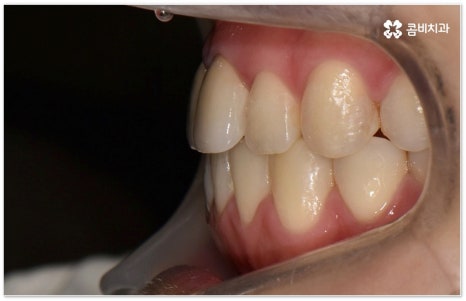

적지 않은 치아교정 비용 역시 치료 시작을 망설이시는 이유가 될 수 있는데요. 그렇다고 해서 치과를 선택할 때 가격적인 메리트만 생각하시기 보다는 교정 치료의 목적이 앞으로 남은 평생 동안 건강하게 사용해야 할 치아의 기능적 심미적인 개선에 있는 만큼 해당 임상 분야의 경험이 풍부하고 뛰어난 노하우를 가지고 있는 의료진과 함께 하는데 초점을 맞추시길 당부드리고 있어요. 또한 처음부터 끝까지 책임 진료하고 사후 관리 역시 철저하게 케어되는 곳인지, 3D CT와 같은 정밀 검진 장비를 갖추고 있는 곳인지 여부도 중요하기 때문에 이런 부분도 함께 살펴보시면 좋을 거예요. 환자 개개인에 맞춤 치료 계획을 세워 무리하지 않은 치아 이동을 통해 전체 구강 건강을 증진시키는 방향으로 교정 치료를 하기 위해서는 이와 같이 의료진의 숙련도 외에도 케어 시스템이나 장비 같은 부분을 꼼꼼하게 체크해 보시는 것이 치과를 선택하는 데 도움이 될 수 있습니다.

치아 교정 치료에 적기가 정해져 있는 것은 아니지만 아래 앞니가 윗 앞니보다 앞으로 물리는 반대교합이나 심각한 주걱턱과 같은 부정교합 등 몇몇 케이스에 있어서는 잇몸뼈가 아직 다 굳어지지 않은 성장기에 치료를 시작하는 것이 상하악의 균형을 잡아주고 교합을 맞추는데 좀 더 효율적일 수 있기 때문에 아이의 치열이 삐뚤어진다면 영구치가 나오기 시작할 때부터 치과에 내원하셔서 검진과 상담을 받아보실 필요가 있어요. 치과에 주기적으로 방문하여 검진 및 스케일링 등을 받으면서 혹시 교정 치료가 필요하지 않은지 여부를 확인하고 언제 시작하는 것이 좋을지 지속적인 관찰을 통해 맞는 시기를 조율해 봐도 좋을 거예요.